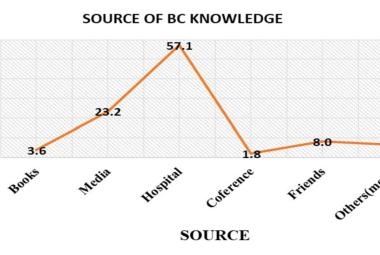

One of the notable complications of impacted mandibular third molar (MTM) is distal caries of the mandibular second molar (MSM) which can eventually lead to its early loss. The present study aimed to investigate the incidence of dental caries in MSM associated with impacted MTM and to propose an assessment protocol for MTM management. Patients’ dental records with dental panoramic tomography (DPT) imaging were studied retrospectively, in total 583 MTM images were evaluated. The presence of MSM distal caries, patient’s details, impaction depth, pattern and angulation of MTM and the distances between distal MSM and mesial MTM were assessed. Logistic regression analysis was performed on the data set. The highest caries incidence was observed in mesioangular impacted MTM (34.1%). Majority of the caries found were Level A (27.9%) and Class II (27.0%). The highest distance between distal MSM and MTM contributing to caries was 0.70-0.99 cm (31.9%). Patients’ age, angulation, pattern and depth of impacted MTM are the predictors which significantly increase the caries incidence in MSM (p<0.05). Prophylactic removal of MTM should be proposed when the distance of mesial impacted MTM and distal MSM is around 0.70-0.99 cm, and is mesially angulated with IIA classification.

Salah satu komplikasi ketara gigi geraham bongsu rahang bawah (MTM) yang tidak tumbuh sepenuhnya (terimpak) ialah karies distal pada geraham kedua rahang bawah (MSM) yang akhirnya boleh menyebabkan kehilangan awal gigi tersebut. Kajian ini bertujuan untuk menyiasat kejadian karies gigi pada MSM yang mempunyai kaitan dengan MTM terimpak serta cadangan penilaian langkah pengurusan berkaitan dengan MTM. Rekod pergigian pesakit bersama gambar panoramik pergigian telah dikaji secara retrospektif, dengan sejumlah 583 imej MTM telah dinilai. Kewujudan karies distal MSM, butiran pesakit, kedalaman impaksi, corak dan sudut MTM serta jarak antara MSM distal dan MTM mesial telah dinilai. Analisis regresi logistik dijalankan ke atas set data. Insiden karies tertinggi diperhatikan pada MTM terimpak mesioangular (34.1%). Kebanyakan karies yang ditemui ialah Tahap A (27.9%) dan Kelas II (27.0%). Jarak tertinggi antara MSM distal dan MTM yang menyumbang kepada karies ialah 0.70-0.99 cm (31.9%). Umur pesakit, sudut, corak dan kedalaman MTM terimpak ialah pembolehubah yang meningkatkan insiden karies pada MSM secara signifikan (p<0.05). Cabutan pencegahan gigi MTM sepatutnya dicadangkan apabila jarak antara MTM terimpak mesial dan MSM distal adalah sekitar 0.70-0.99 cm, dan MTM bersudut mesial dengan klasifikasi IIA.